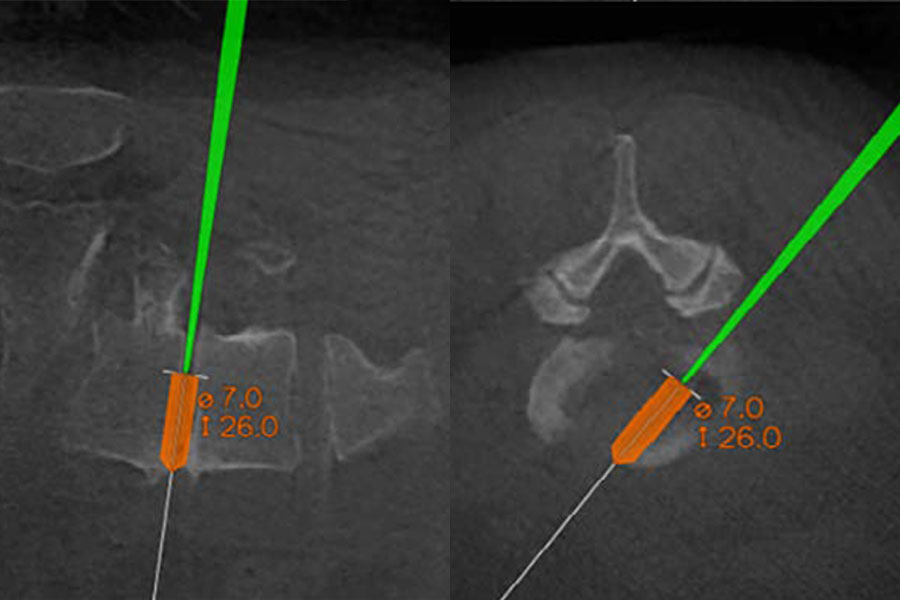

The First 3D-Navigation-Guided Endoscopic TLIF in NYC

Earlier this year, Dr. Ibrahim Hussain, a neurological spine surgeon at Och Spine at NewYork-Presbyterian, performed the first 3D-navigation-guided endoscopic transforaminal lumbar interbody fusion (TLIF) in New York City. This innovative procedure for treating lumbar degenerative pathologies relies on 3D navigation to map a trajectory that avoids nerve injury and helps plan and customize the size of the implant. This collapsed interbody “cage” is expanded after placement inside the disc space under endoscopic visualization. In contrast to open TLIF and minimally invasive TLIF, 3D endoscopic TLIF requires a smaller incision, minimal bone and muscle dissection, and less sedation, resulting in a faster, less painful recovery.

3D-navigation-guided trajectory mapping for the planning and sizing of an implant.